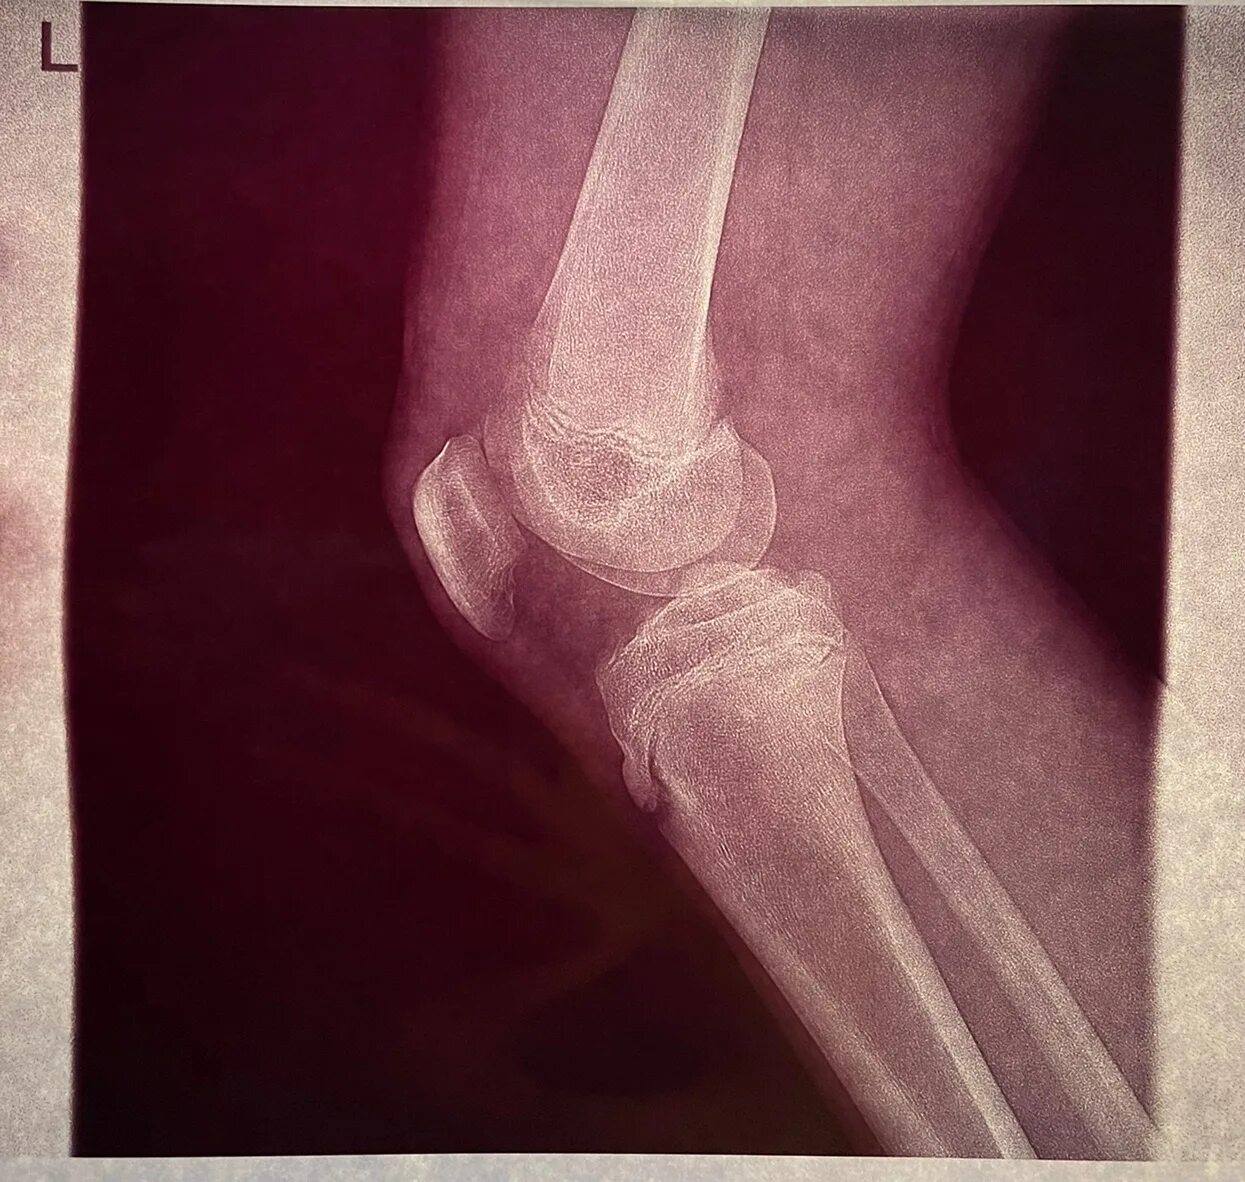

Болезнь шляттера код по мкб